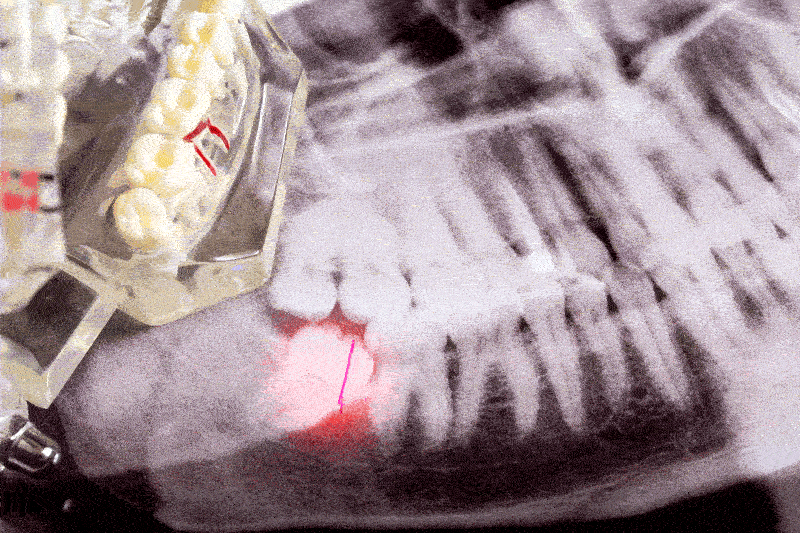

Wisdom teeth removal is a common and straightforward procedure that begins with an oral examination and X-rays. This initial step helps determine the position and condition of the teeth and whether removal is necessary. During the procedure, local anesthesia is used to numb the area, though some cases may require general anesthesia for added comfort. The oral surgeon makes an incision in the gum tissue to expose the tooth, removes it, and sutures the wound to promote healing.